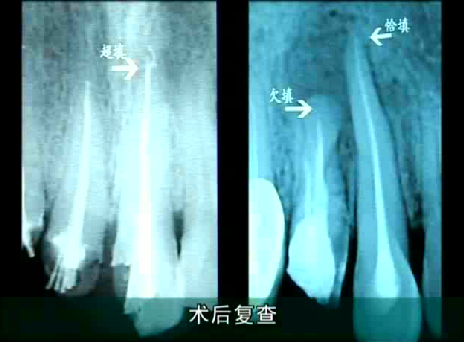

根管治療複查充填超填、恰填和欠填的區別